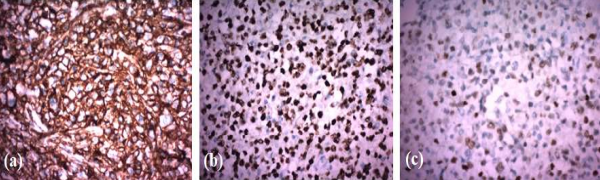

Blood count showed the following: haemoglobin, 7.4g/dl; white cell count, 8,900 cells/cu mm and platelets, 3.18 lakhs/cu mm. The results of his renal and liver function tests were within normal limits. Inflammatory markers, Erythrocyte sedimentation rate and C-reactive protein were markedly elevated to 80 mm and 260.6 mg/L, respectively. Septic workup including blood and urine cultures was negative. Procalcitonin was normal (0.28 ng/ml). Chest X-ray was clear. Ultrasound abdomen revealed a 6 × 4.6 cm well defined heterogeneous mass with air pockets in right side of pelvis along with few enlarged iliac lymph nodes suggestive of abscess. Contrast enhanced CT scan of abdomen was done to further characterise the lesion. It showed a long concentric bowel wall thickening of distal ileum with surrounding bulky lymphadenopathy (Fig. 1a and b).

Figs. 1a and b. CECT abdomen axial and coronal images respectively showing aneurysmal dilatation of distal ileum marked with arrow.